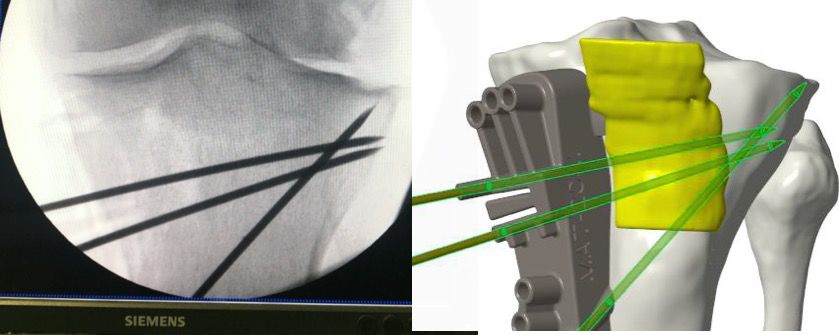

- Positing two k-wires to verify PSCG position and secure Tibia’s hinge from sawing (Figure 6)

- Saw blade guidance to allow very accurate angulation relatively to tibial morphological parameters (Figure 7)

- Map of 6 to 8 screw holes to allow guided drilling for screw holes which will match to the screw position of the final plate after the correction (Figure 8)

Positioning PSCG and Osteotomy:

Once the PSCG is inserted two K-wire are drilled in the dedicated holes, for temporary fixation. This should be carefully controlled by fluoroscopy (Figure 11) to confirm the optimal position of the Guide. Then the screw holes are drilled, and the guide is rigidly fixed on the tibia using six 4 mm Pins. During the sawing process a small Hohmann retractor is used to retract the MCL, to get good access to the cutting plane.